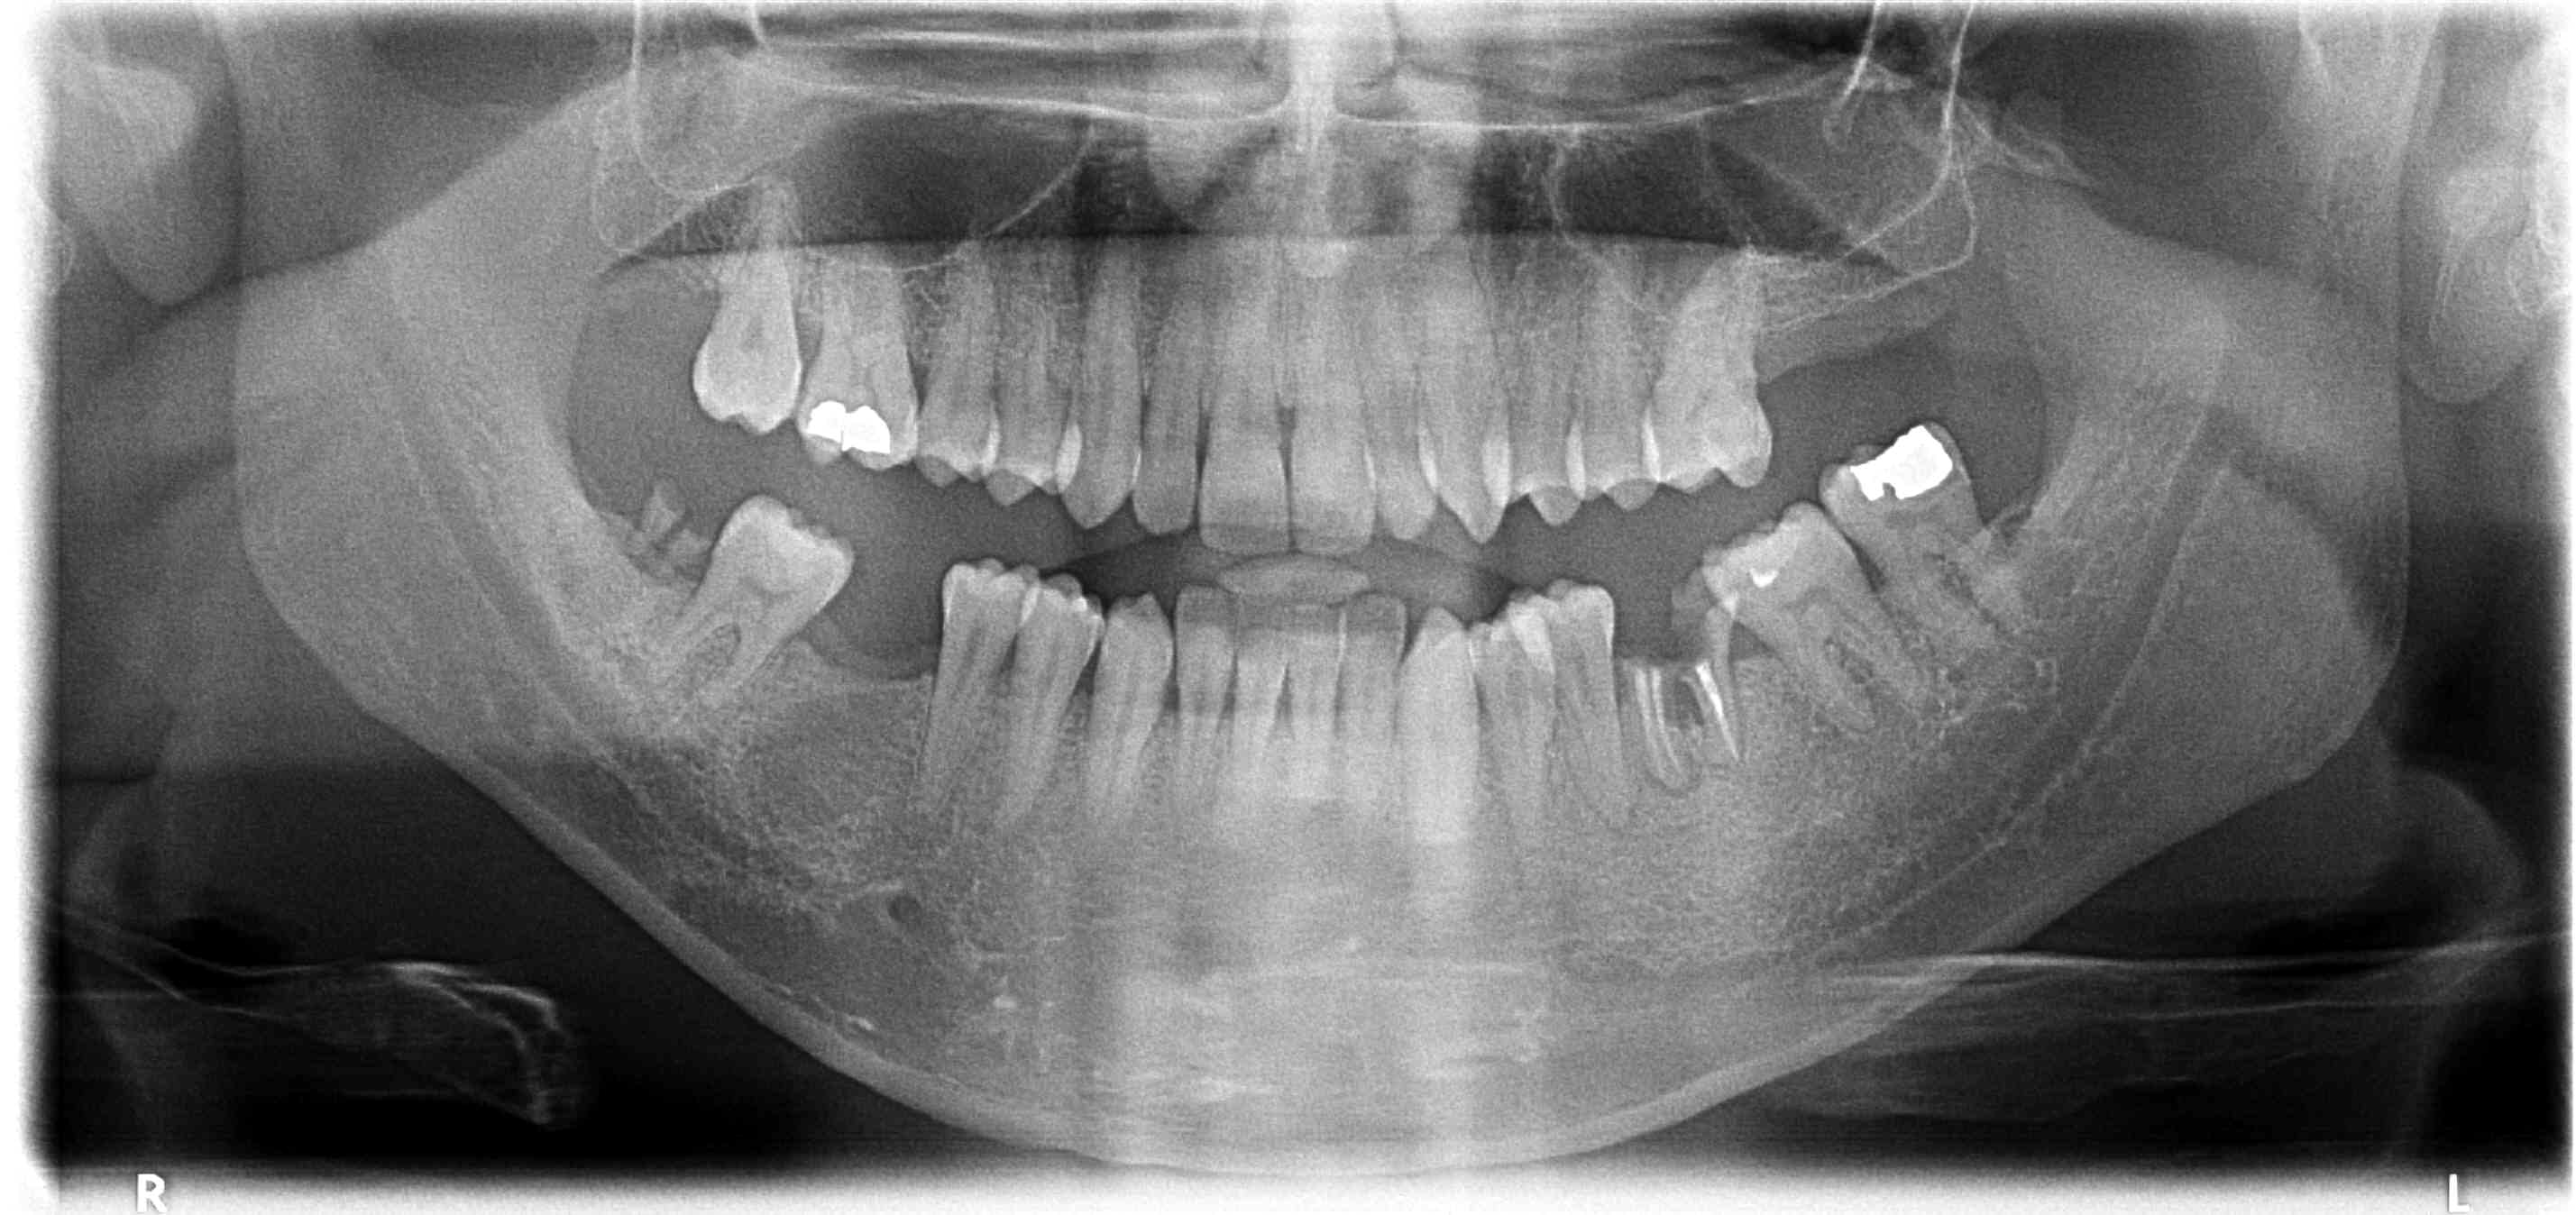

Patient 40, revu aujourd'hui après disparition dans la nature, en urgence pour douleurs sur 38.

Dent mobile douloureuse à la percu, sans antagoniste, je dirais nécrosée, décision est prise d'extraire.

Anesthésie, pas de contact osseux mais vraiment pas ... je me dis grosse infection, on continue ..., extraction sans gros problème. Mais je me dis que c'est quand même louche, je refais une retro un peu plus distale, j'y vois pas grand chose de plus, alors je fais une pano (moisie, je sais pas top le matos) et là, l'image n'est quand même pas nette, nette ... (j'aime pas les lobules).

La première pano est celle d'il y a un an, la deuxième, celle du jour après exo de 38.

Quand on a le nez dessus, on voit un truc en distal, l'année dernière. C'est pas bien joli effectivement.

Oui, j'ai eu la même réaction quand je suis revenu sur la pano d'il y a un an, en me disant merde, je suis passé à côté de quelque chose. Mais pas flagrant.

Grosse perte osseuse, sur un contexte tabac, 8 nécrosée+poche distale, hygiène pas dingue... ça peut.

Je le répète, même si en me relisant ce n'est pas si clair, on ne peut à mon sens pas exclure qu'il s'agisse (juste) d'une belle lésion endo paro; l'aspect n'est pas beau, mais j'en ai déjà vu un paquet de cette taille là.

En vrai, si je n'avais aucune notion de contexte, l'image m'aurait évoqué en premier lieu une ostéo nécrose. Mais là, rien ne colle.